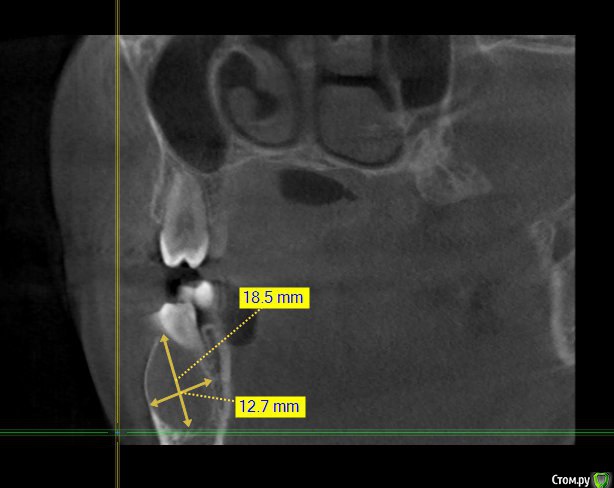

Kovalov Igor Опубликовано 14 июля, 2015 Поделиться Опубликовано 14 июля, 2015 (изменено) Уважаемые коллеги приветствую Вас! Встал вопрос стоит ли трогать фолликулярную кисту или наблюдать?Пациентка моя сестра, фолликулярная киста была случайной находкой, обнаружил ортодонт, отправил в областную больницу г. БелгородаВ детской ЧЛХ отказались, отправили в Харьков, это был 2013 год ещё. Во взрослой ЧЛХ не взялись, по возрасту. В детской члх сделали КТ, снимки и панораму прилагаю.Ps: картина за 2 года стала получше, но КТ сделают позже, есть внеротовой Rg снимок. Дело в том что я живу от сестры более 3000 км., сам бы это дело вскрыл амбулаторно, цистэктомия, графт+мембрана если гноя не будет... либо под йодоформом. Но вопрос стоит ли? и как по протоколу, каков Ваш план лечения? Депульпировать ли зубы 45-46? Изменено 14 июля, 2015 пользователем Kovalov Igor Ссылка на комментарий

Kovalov Igor Опубликовано 14 июля, 2015 Автор Поделиться Опубликовано 14 июля, 2015 вот Rg свежий. Вроде граница фолликулярной кисты уменьшилась.Как сделают КТ поделюсь тут... Буду признателен за ответы! Ссылка на комментарий